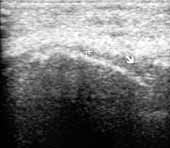

Рис. 7. Ревматоидный артрит, III стадия; резкое истончение

гиалинового хряща медиального мыщелка (+), наличие над ним жидкости

(стрелка), уплощение суставной поверхности.

Рис. 14. Деформирующий остеоартроз, III стадия. Выраженное

неравномерное истончение гиалинового хряща (+).